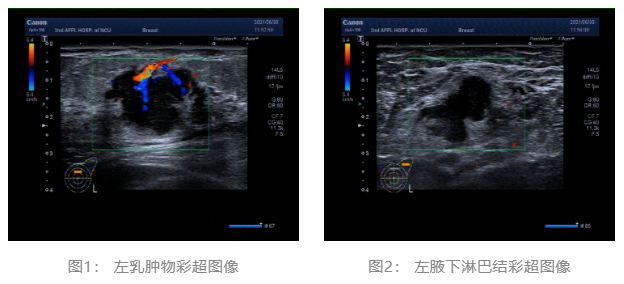

2021.06.30 乳腺彩超:左侧乳腺低回声团块,BI-RADS-US 4c类。左侧腋窝肿大淋巴结。(图1、2)

▌治疗前后影像学对比:

乳腺彩超:

术前评估:新辅助治疗期间患者无明显不适,一般状况可。新辅助治疗后左乳房肿瘤及腋下肿大淋巴结退缩明显,疗效评估PR,未发生不良事件,择期可行左乳癌改良根治术。